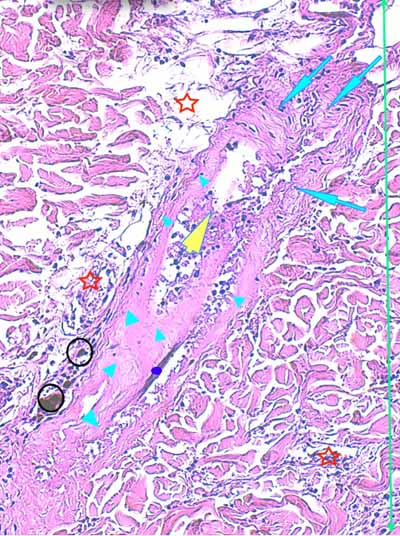

Biopsies cutanées

Sur l’une des biopsies, l’épiderme et les structures annexielles sont nécrosées ainsi que de larges plages de fibres de collagène dans le derme profond (Fig6). Dans le derme périannexiel, on observe une discrète hypercellularité diffuse sous la forme de cellules pycnotiques (Fig2,3,13,14). En profondeur, dans l’hypoderme, on observe une dilacération des septa conjonctifs interlobulaires et des adipocytes par un matériel sérofibrineux, parsemé d’une poussière nucléaire entourant parfois des structures vasculaires, artériolaires et veineuses, de moyen calibre dont la lumière est occupée par un thrombi fibrineux et dont les cellules endothéliales apparaissent vacuolisées (Fig7,8,9). Sur les autres biopsies, l’épiderme montre des lésions de dégénérescence réticulaire (Fig3,4,5). Cet aspect est associé à un décollement épidermique multifocal(Fig2,3). Le derme superficiel est œdémateux (Fig3,4,5). Au sein des unités annexielles, on observe plusieurs follicules pileux dont la gaine épithéliale folliculaire externe, est plissée sur toute sa longueur. La tige pilaire présente dans le canal pilaire est elle-même circonvolutée, fracturée, la cuticule effritée (Fig2,10,11,12) . Le cycle folliculaire est normal, la phase anagène prédomine. Autour des structures annexielles, on observe de petits foyers de taille variable, nécrotiques, avec une poussière cellulaire et probablement un matériel fibrinoïde (Fig13,15). On perçoit encore la silhouette de certaines structures vasculaires dont la lumière semble obstruée de thrombi. On en retrouve, dans les septa conjonctifs interalvéolaires, des lobules adipeux. A noter, que sur l’une des biopsies, se trouvent incluses dans le tissu adipeux, des tiges pilaires tortueuses. Dans plusieurs territoires dermiques nécrotiques, on observe, au fort grossissement à l’objectif à immersion, des silhouettes vasculaires tapissées de reliquats de cellules endothéliales, au cytoplasme vacuolisé avec chromatolyse nucléaire. En périphérie, les fibres de collagène prennent un aspect coagulé, basophile. Elles montrent une multitude d’éléments bacillaires associés à des dépôts acidophiles, probablement fibrinoïdes (Fig16).

Photo 14 (Hémalun-Eosine X100) : à la jonction dermo-hypodermique,

un bulbe folliculaire anormal est en rapport direct avec une plage cellulaire inflammatoire.

Légendes de la Photo 14 :

- Étoile rouge vide : adipocyte

- Étoiles rouges pleines : vaisseaux sanguins (une erreur au milieu à droite = adipocyte)

- Pointe de flèche jaune : reliquat de bulbe pilaire fracturé et désolidarisé du reste du follicule pileux

- Flèches turquoises : plage cellulaire inflammatoire peuplée de cellules pycnotiques et de granulocytes neutrophiles, en étroit rapport avec le reliquat de bulbe folliculaire

- Double flèche verte : derme

- Double flèche bleue : hypoderme

Photo 13 (Hémalun-Eosine X200) : dans le derme, on remarque des plages

cellulaires inflammatoires, peuplées de granulocytes neutrophiles,

en étroit rapport avec les unités annxielles folliculo-sébacées.

Légendes de la Photo 13 :

- Étoiles rouges vides : glandes sébacées

- Étoiles rouges pleines : follicules pileux

- Pointe de flèche jaune : canal pilaire

- Flèches turquoises : plage cellulaire inflammatoire peuplée de cellules pycnotiques et de granulocytes neutrophiles